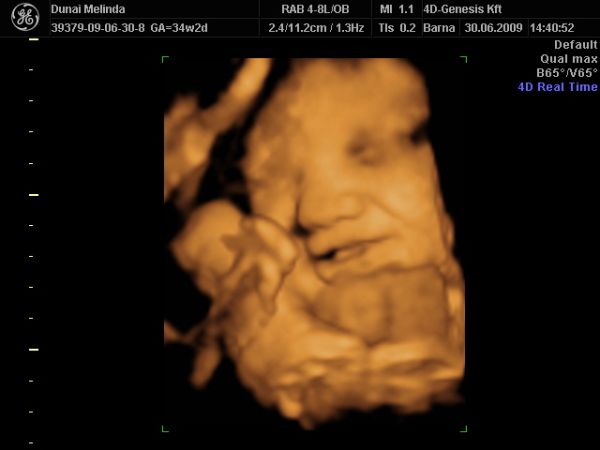

most elvileg megint vagy 10 hétig nem nézik Bogyót, 28-30. héten van megint kötelező UH. Iktass be közte egy 4D-t, ha tudsz. Én továbbra is javaslom a 4D Genesis-t, mi kedden megyünk másodjára. Olyan kedves az a nő, annyi mindent megnéz, nem csak a baba állapotát, hanem a tied is, és tuti nem enged úgy el, hogy ne hozza valahogy össze, hogy megkukkoljátok a lába közét, ha szeretnéd.

KépKép